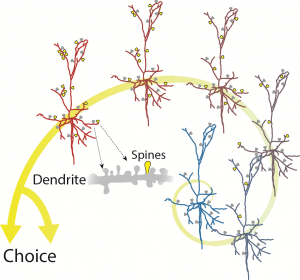

Δεναξά Μυρτώ, Επιστημονικός Υπεύθυνος του ερευνητικού έργου με τίτλο: «Πώς καθορίζονται τα λειτουργικά χαρακτηριστικά συγκεκριμένων ομάδων νευρικών κυττάρων του εγκεφάλου, που ονομάζονται ενδονευρώνες»

Η ισορροπία μεταξύ διέγερσης και κατάστολής είναι θεμελιώδης για τη βέλτιστη λειτουργία του εγκεφάλου. Οι ενδονευρώνες αποτελούν την κύρια πηγή αναστολής των διεγερτικών νευρικών κυττάρων του εγκεφαλικού φλοιού. Αλλαγές στον αριθμό ή την λειτουργία τους έχουν συσχετισθεί με ποικίλες νευροαναπτυξιακές και νευροψυχιατρικές διαταραχές, όπως επιληψία, σχιζοφρένεια και διαταραχές του φάσματος του αυτισμού.

Η ισορροπία μεταξύ διέγερσης και κατάστολής είναι θεμελιώδης για τη βέλτιστη λειτουργία του εγκεφάλου. Οι ενδονευρώνες αποτελούν την κύρια πηγή αναστολής των διεγερτικών νευρικών κυττάρων του εγκεφαλικού φλοιού. Αλλαγές στον αριθμό ή την λειτουργία τους έχουν συσχετισθεί με ποικίλες νευροαναπτυξιακές και νευροψυχιατρικές διαταραχές, όπως επιληψία, σχιζοφρένεια και διαταραχές του φάσματος του αυτισμού.